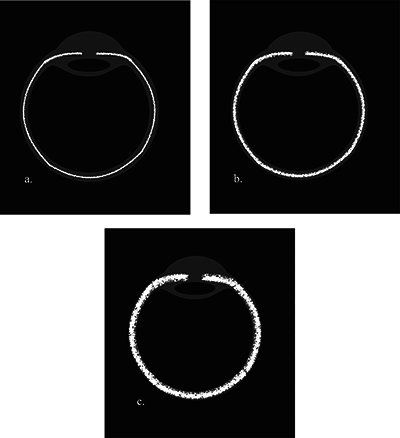

目的:对比增强FLAIR脂肪抑制(CE-FLAIR-FS)成像有可能提高葡萄膜疾病的诊断准确性,并最终提供更好的患者管理。本研究旨在确定 CE-FLAIR-FS 成像与对比增强 T1 加权成像(CE-T1WI)在评估儿童葡萄膜炎患者时的诊断价值。材料和方法:研究回顾性地纳入了21名接受全脑磁共振成像(MRI)(包括CE-FLAIR-FS和CE-T1WI)检查的葡萄膜炎患儿。我们评估了葡萄膜束对比度增强与增厚、玻璃体信号异常以及伴随的脑部异常。与 CE-T1WI 和 CE-FLAIR-FS 图像相比,葡萄膜增强强度被半定量地评估为轻度、中度和明显葡萄膜炎。结果显示全葡萄膜炎(61.9%)是最常见的解剖位置,其中大部分是特发性的(47.6%)。在 42 眼临床葡萄膜炎患者中,21 眼(50%)在 CE-FLAIR-FS 图像上观察到葡萄膜束增强,5 眼(11.9%)在 CE-T1WI 图像上观察到葡萄膜束增强。经检测,CE-FLAIR-FS 对泛葡萄膜炎的灵敏度相当高(80.8%)。CE-FLAIR-FS的受累眼数和增强程度更高(P < 0.001)。在评估葡萄膜炎的严重程度时,CE-FLAIR-FS 的分级明显高于 CE-T1WI,灵敏度更高(P < 0.001,Z:-4.347)。三名患者在 CE-FLAIR-FS 图像上出现玻璃体异常信号,但在 CE-T1WI 图像上却没有。结论CE-FLAIR-FS在诊断小儿葡萄膜炎、确定葡萄膜炎症的累及范围和严重程度以及指导适当的治疗方面发挥着重要作用。将其作为标准序列加入葡萄膜病变的常规核磁共振成像方案将大有裨益。

Objectives: Contrast-enhanced FLAIR fat-suppressed (CE-FLAIR-FS) imaging can potentially increase the diagnostic accuracy of uveal diseases and ultimately provide better patient management. This study aimed to determine the diagnostic value of CE-FLAIR-FS imaging versus contrast-enhanced T1-weighted imaging (CE-T1WI) in the assessment of pediatric patients with uveitis. Material and methods: Twenty-one children with uveitis who underwent whole brain magnetic resonance imaging (MRI), including CE-FLAIR-FS and CE-T1WI, were retrospectively included in the study. We evaluated the presence of uveal tract contrast enhancement with thickening, vitreous humor signal abnormality, and accompanying brain abnormalities. The uveal enhancement intensity was assessed semiquantitatively as mild, moderate, and marked uveitis compared to CE-T1WI and CE-FLAIR-FS images. Results: Panuveitis (61.9%) was the most frequent anatomic location, and most of them were idiopathic (47.6%). Of the 42 eyes with clinical uveitis, enhancement of the uveal tract was observed on CE-FLAIR-FS images in 21 eyes (50%), while in 5 eyes (11.9%) on CE-T1WI. The sensitivity of CE-FLAIR-FS in panuveitis was detected to be quite high (80.8%). The number of affected eyes and enhancement degree were found to be higher on CE-FLAIR-FS (p < 0.001). In assessing the severity of uveitis, CE-FLAIR-FS grades were significantly higher and more sensitive than CE-T1WI (p < 0.001, Z: -4.347). Three patients had vitreous abnormal signals on CE-FLAIR-FS images, but none on CE-T1WI. Conclusion: CE-FLAIR-FS plays a significant role in the diagnosis of pediatric uveitis, identifying the involvement and severity of the uveal inflammation and guiding the appropriate management. It would be beneficial to add it as a standard sequence to the routine MRI protocol for uveal pathologies.